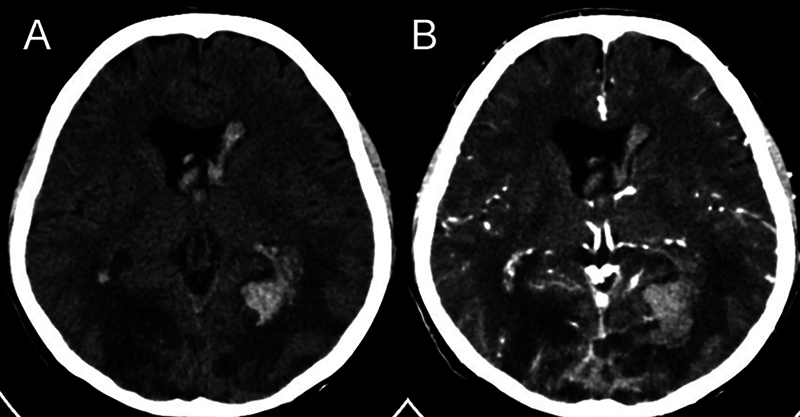

脑曲霉菌病是一种机会性真菌感染,在免疫功能正常的患者中极为罕见。这些感染的主要病因通常涉及鼻腔和血液传播。一名 62 岁的男性患者注重养生,出现间歇性、非进行性枕部头痛、全身阵挛强直发作和意识改变。计算机断层扫描显示,两侧枕叶有多个边缘强化的小病灶,两侧枕叶邻近蝶窦和后上矢状窦汇合处有血管源性水肿。在这个病例中,发现了继发于脑曲霉菌病的上矢状窦血栓形成,这种情况以前从未在这个特定部位确诊过,但可以通过手术干预加以控制。手术切除和抗真菌治疗相结合,取得了良好的疗效。患者的预后很大程度上取决于早期诊断和及时、积极的治疗。

Cerebral aspergillosis is an opportunistic fungal infection that is exceedingly rare in immunocompetent patients. The primary etiological locations for these infections typically involve the nasal cavity and hematological dissemination. A 62-year-old male, focused on wellness, presented with intermittent, nonprogressive headaches in the occipital region, generalized clonic-tonic seizures, and altered consciousness. A computed tomography scan revealed multiple small rim-enhancing lesions in both occipital lobes, with vasogenic edema in both occipital lobes adjacent to the confluence of the sinuses and the posterior superior sagittal sinus. In this case, superior sagittal sinus thrombosis secondary to cerebral aspergillosis was discovered, a condition not previously diagnosed in this specific location but manageable through surgical intervention. A combination of surgical resection and antifungal therapy resulted in favorable outcomes. The prognosis for patients depends significantly on early diagnosis and prompt, aggressive treatment.